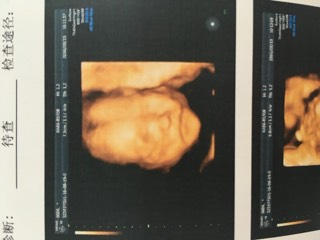

公立医院提前两个月都约不到四维,只好去私立医院做了,老公能够进去陪同哟,我躺着,他坐旁边,我们面前一个大的屏幕,医生在肚子上探测,屏幕上就出现宝宝动态,看的好清楚,医生在照宝宝腿的时候给了两个镜头,我看到中间那一小坨了,哈哈,老公看不懂,只有医生带着说的时候才知道哪是哪,笨!小猴子一开始不太配合,老用手遮住脸,后来医生在别处按了下才让他变了下动作,整个过程差不多20多分钟,也算顺利吧,把结果给家人看,都说宝宝像我,这下巴和嘴巴像极了,哈哈,就是小猴子在肚子里瞎动,脐带绕颈一圈,医生说不要紧,现在宝宝还小,等28周左右的时候再看,希望到时候小猴子能够顺顺利利的哟。